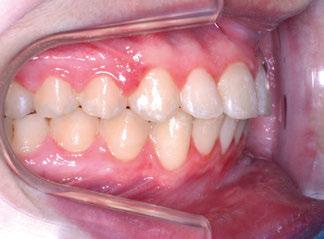

Figuras 1-3.

La niña de las figuras 1 a 3 presenta una leve asimetría facial con patrón braquifacial por tercio inferior disminuido y mentón desviado ligeramente hacia la derecha; los labios son competentes y en sonrisa apenas se exponen los incisivos. El perfil es excesivamente convexo,

La exploración intraoral (figuras 4 a 8) revela una Clase II molar y canina completa, líneas 1/2 dentarias superior 0,5 mm e inferior 1 mm ambas desviadas hacia la derecha, los incisivos superiores excesivamente protruidos y vestibulizados (seguramente debido a la interposición del labio inferior), resalte de 13 mm y sobremordida 2/3 de corona. La discrepancia oseodentaria

inferior es de -3,5 mm y la curva de Spee de 4 mm.